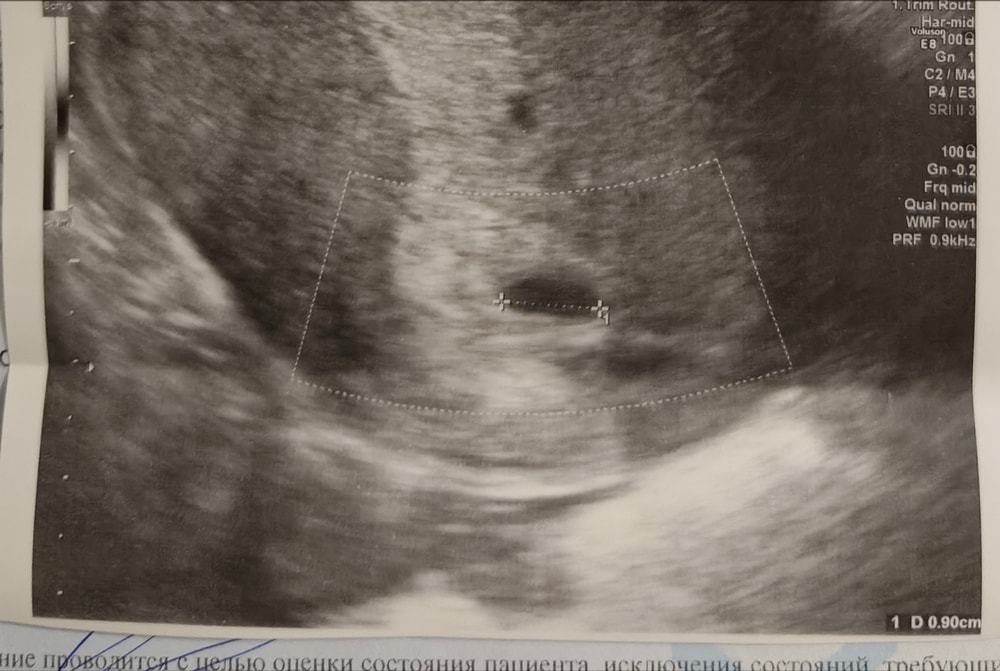

Озадачилась я ночным разглядыванием вчерашнего снимка, даже спросила ai мне помочь, теперь буду с нетерпением ждать ещё двух недель 😂 чего тесты на двойню не придумали, такой бизнес пропадает

Меня уже по-всякому переспросили и про срок, и про цифры, может, у меня правда что-то аномальное?😂

Месячные - завтра, ХГЧ утром был 1404.

Я-то надеялась на ХГЧ 1404, хоть и за день до задержки, остановиться и пройти УЗИ, но сказали что рано.